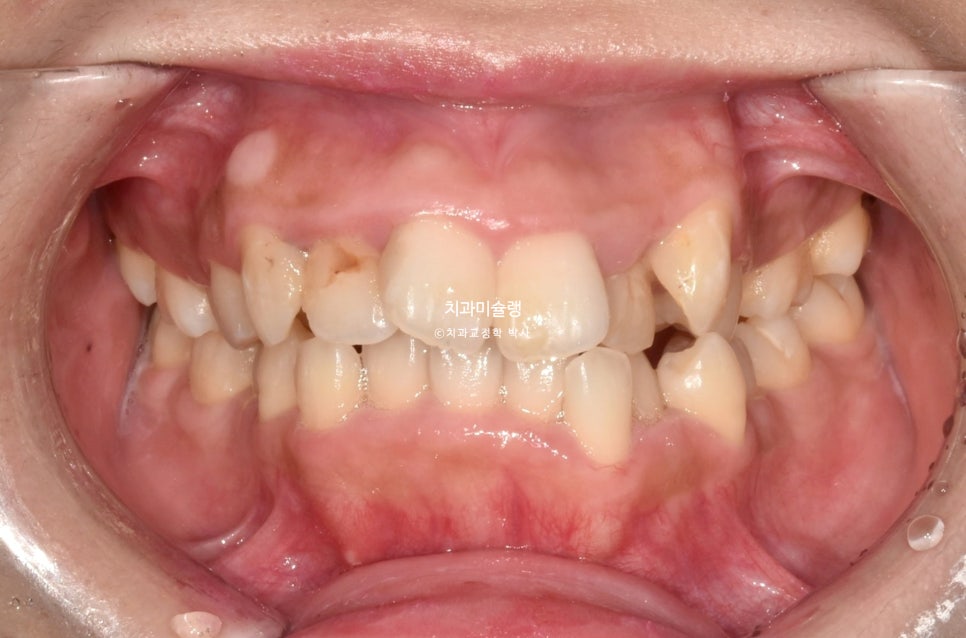

2023년 여름, 인비절라인 교정을 원해서 온 환자분 입니다.

닷니와 반대교합이 보입니다.

앞니에 갈색 부분은 예전에 레진으로 충치치료한 부분이 변색된 것입니다.

작은어금니 쪽에는 반대교합도 보입니다.

악궁이 소구치 부위가 안으로 쓰러져 찌그러진 모양입니다.

앞니뿐 아니라 어금니에도 여기저기 충치가 보입니다.

총생 (치아 삐뚤한 정도) 가 심하고 돌출감도 있어 작은어금니 4개 발치가 불가피한 상황입니다.